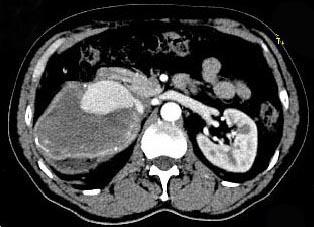

问题 男,48岁,反复腰酸、腰痛伴镜下血尿2年,加重3天,无尿频、尿急、尿痛,无低热、盗汗、咳嗽,右肾区叩击痛,CT检查如图所示,应诊断为 ( )

选项 A、右肾错构瘤 B、右肾盂癌 C、右肾癌 D、急性右肾内血肿 E、右肾动脉瘤

答案 E